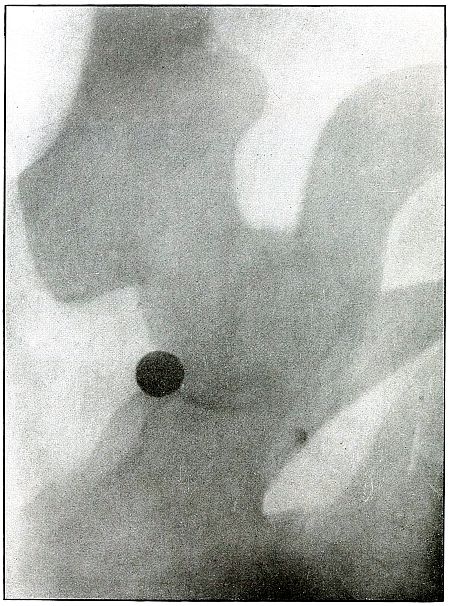

Plate 48.

[Pg 107]

Rifle—Plate 48.

LOWER EXTREMITY.

Gunshot Wound of the Thigh,

with Lodgment of the Bullet.

Wound of entrance, outer aspect of the thigh at the junction of the

upper and middle thirds.

The slight penetration without bone injury and with slight deformity

of the nose of the bullet indicates that the wound was caused by a

ricochet shot at extreme range, after its energy was almost spent.

With the posterior aspect of the thigh next to the plate, the dense

shadow and the nearly normal size of its outline indicate that the

bullet was in the same relative position and that it lay posterior to

the neck of the femur.

As such wounds are rarely infected, the treatment is conservative,

and a search for the missile is only justified by serious infection,

pain, or impaired function.